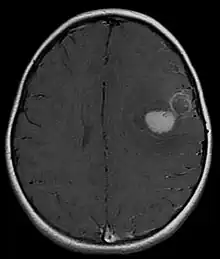

| Micrograph of an H&E stained section of a peripheral PNET. | |